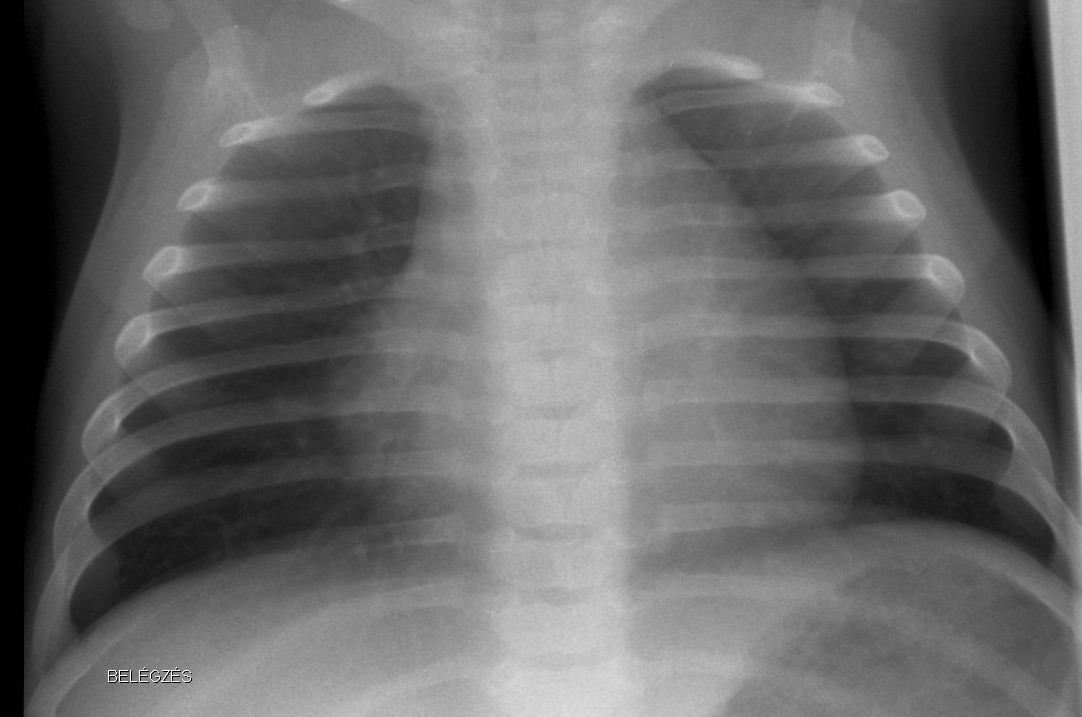

18.2. Radiologic diagnostics of the chest

Normal newborn lungs: a newborn’s chest goes through some fundamental changes during the first days of extra-uterine life. The heart is relatively rounded, characterized by the dominance of the right side. The cardio-thoracic index taken in a mid-inspiratory state is between 0.55-0.62. Expiratory state can lead to diagnostic mistakes.

Bony thorax: the ribs are horizontal and the sagittal and horizontal diameters of the chest are very close to each other.

1.b. Inspiratory state, the lung is transparent, the heart is normal sized. Ribs run horizontally in infants.